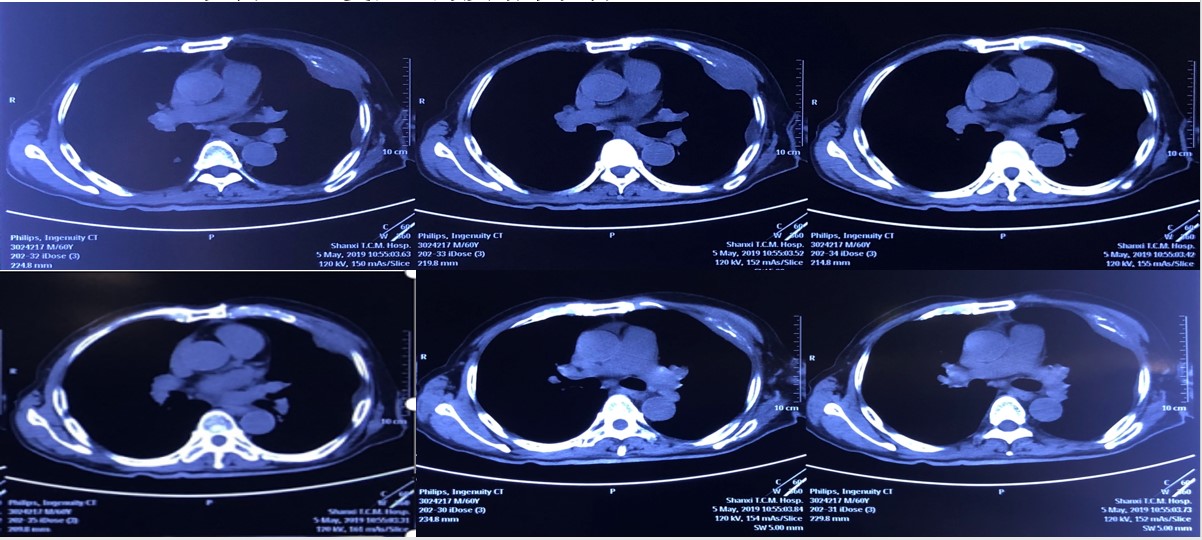

患者术后恢复良好,自2018年11月起口服培唑帕尼(维全特),期间出现胸水、恶心、食欲不振、全身乏力、体重下降等不良反应。患者于2019年4月出现咳嗽咳痰、气紧、伴左背部疼痛,精神萎靡症状。于山西医科大学第一医院行全身检查,骨扫描结果示左侧肩胛骨及肋骨骨质代谢异常病变灶,考虑为恶性病变骨转移;肺CT结果提示为:肺转移,胸腔积液(图1)。

图1. CT复查结果